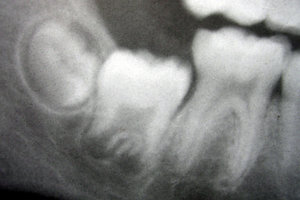

El primordio o germen dentario es una agregación de células en diferenciación para constituir el futuro diente. Estas células derivan del ectodermo del primer arco branquial y del ectomesénquima de la cresta neural.El primordio dentario se organiza en tres zonas: el órgano del esmalte, la papila dentaria y el folículo dentario.

Aunque este proceso sucede a distintas edades, según el individuo, existe una línea temporal generalizada válida. Típicamente, los humanos poseen 20 dientes deciduos y 32 permanentes. La erupción sucede en tres fases. Durante la primera, el estadio de dentición temporal, solo éstos dientes son visibles. Cuando el primer diente definitivo sale, existen ambos tipos en la boca, y se habla de una dentición transicional o mixta. Después de que la última pieza de leche caiga, se dice que la dentición es ya permanente.

Como norma general, cada seis meses salen cuatro dientes nuevos; los dientes mandibulares se originan antes que los maxilares: y salen antes en mujeres que en varones. Durante la fase de dentición decidua, los gérmenes de dientes permanentes se desarrollan bajo los primeros, cerca del paladar o de la lengua.